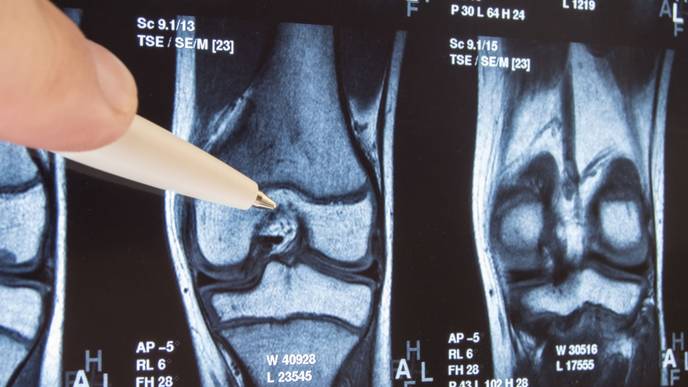

As the first trial sponsored and directed by the Arthritis Foundation, the PIKASO Trial will measure changes in joint structure using advanced imaging techniques and functional improvements using cutting-edge biomechanics measurements. The trial will bring together renowned scientists from the following institutions:

- Cleveland Clinic, the imaging center that will coordinate the collection and analysis of MRI data